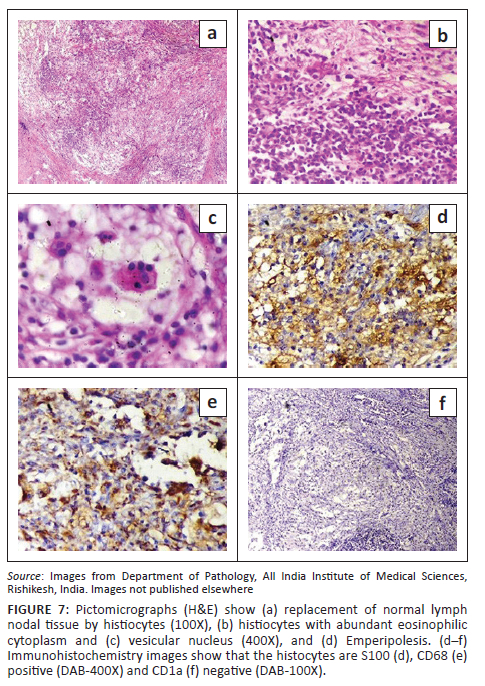

The patient underwent an excision biopsy of the submental lymph nodes under general anaesthesia. Histopathological examination showed multiple partially encapsulated lymph nodes with loss of normal architecture and markedly widened sinuses. The sinuses of the lymph nodes were distended with lymphocytes, plasma cells and histiocytes. Marked 'emperipolesis' was seen. The histiocytes were positive for CD68 and S100 and negative for CD1a (Figure 7). These pathological features led to a definitive diagnosis of RDD. Osseous involvement was excluded by an unremarkable bone scan.

The imaging manifestations of RDD (summarised in Table 1) are variable, and nonspecific and histopathology is necessary for a definitive diagnosis. Rosai Dorfman disease is a histiocytic disorder with an abundance of histiocytes. The classic pathological feature termed 'Emperipolesis' refers to phagocytosis of lymphocytes, polymorphonuclear leukocytes, plasma cells or erythrocytes within the cytoplasm of the histiocytes. On immunohistochemistry, the histiocytes are positive for S100 and CD68 and negative for CD1a.1,10 All these features were seen in the presented case and helped clinch the final diagnosis.